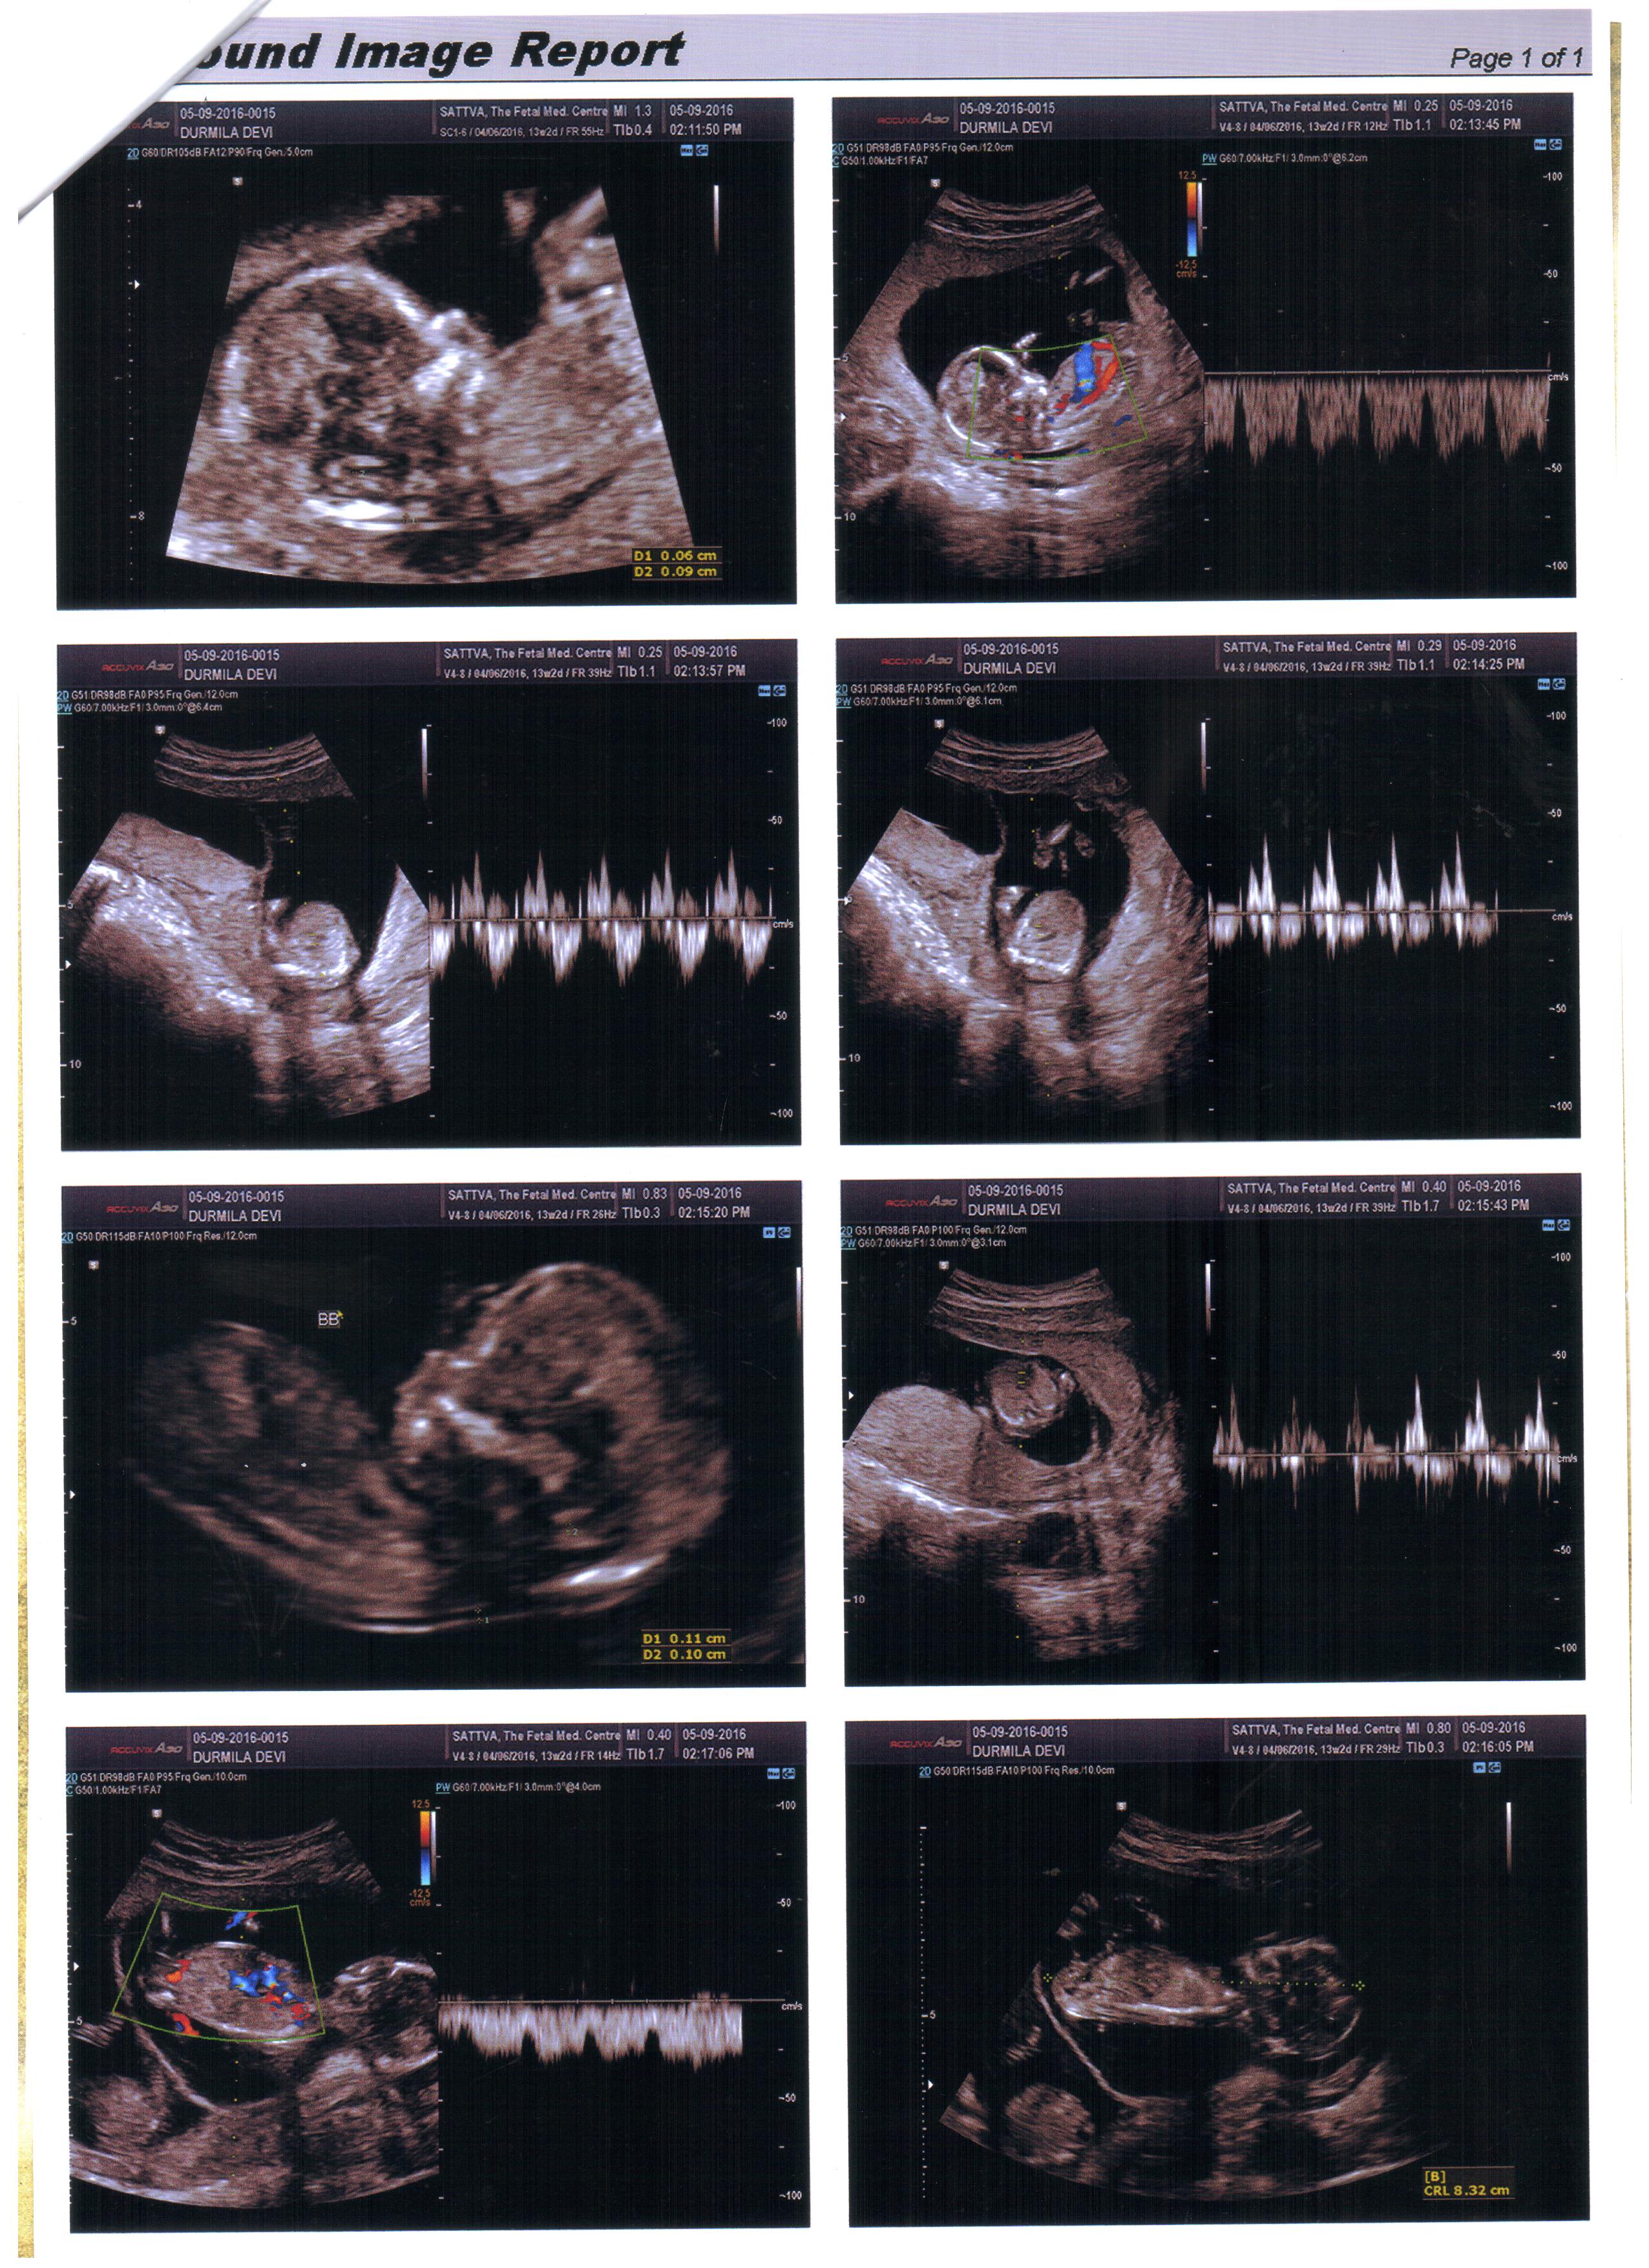

Can you guys pls guess for me. I m posting 8week transviginal scan of my fraternal twins.Attachment 33190

I m posting another scan 13 week Attachment 33191

I'm guessing boy on the bottom two pics. Is that the same baby or two different babies? Which twin is which? Perhaps you could place a bigger picture of the two bottom pics and explain which twin is on which picture :) Thanks!

First two pics r baby A n last two pics is baby B. But thanx to both of you, I have a daughter, I want boys to complete my family. Just pray for me gals.

I'm thinking baby B is a boy, baby A I'm not seeing any gender clues. More pics of baby A?